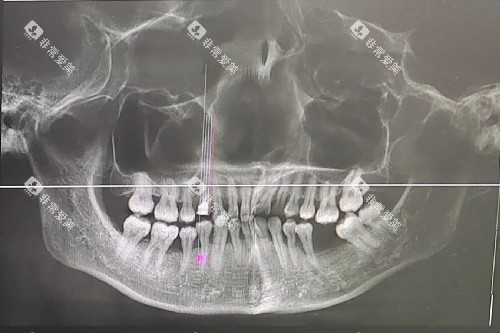

科室配备了一系列可靠的口腔诊疗设备,如智能化口腔全景机、种植牙系统、牙齿美白设备等,为患者提供各方位、高质量的口腔诊疗服务。

在种植牙方面,科室引进了多种比较有名品牌的种植体,价格涵盖了不同的档次,患者可以根据自己的经济实力进行选择。

同时,医生娴熟的种植技术能够确保种植结果,大大提高了种植牙的成功几率。